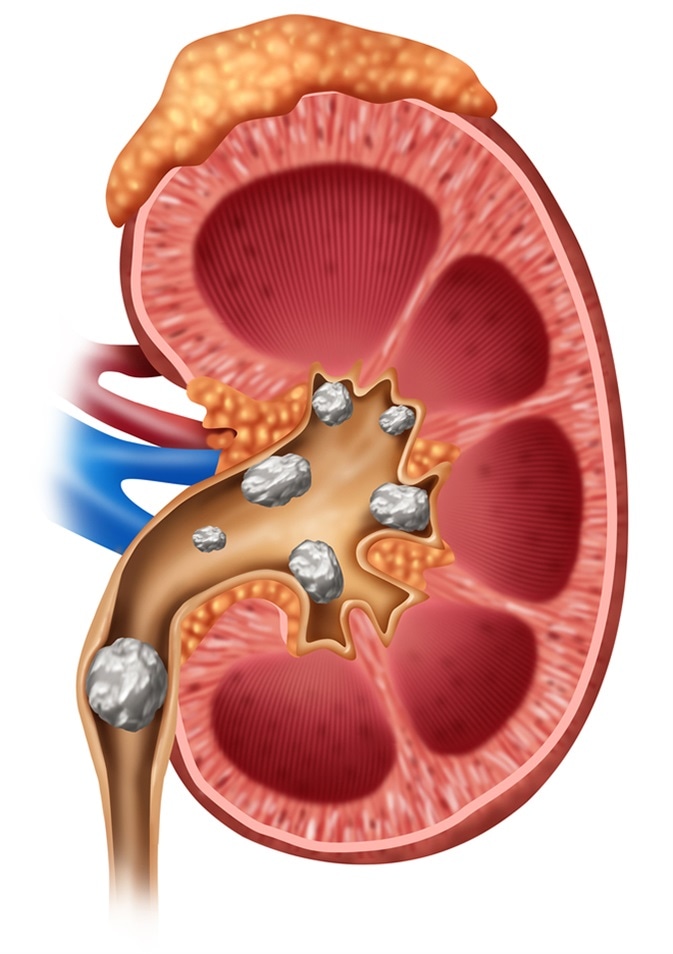

Kidney stones illustration: Image Credit Lightspring / Shutterstock